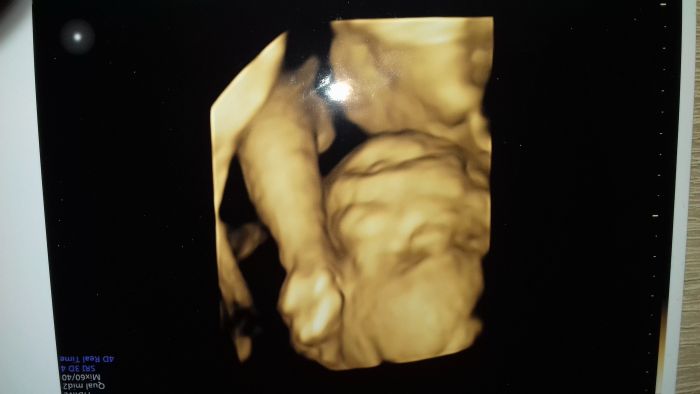

Tak už za sebou mam i druhý screening a vse v pořádku. Sice víme, že to bude holčička, ale i dnes už to bylo moc pěkně vidět. Mala by mela mit asi 448g už.Nejdřív to vypadalo, že 3d fotku nebudeme ani tady mit,protoze mala mela před obličejem pupeční šňůru,ale na poslední chvíli se to povedlo tak tu dávám fotku male.